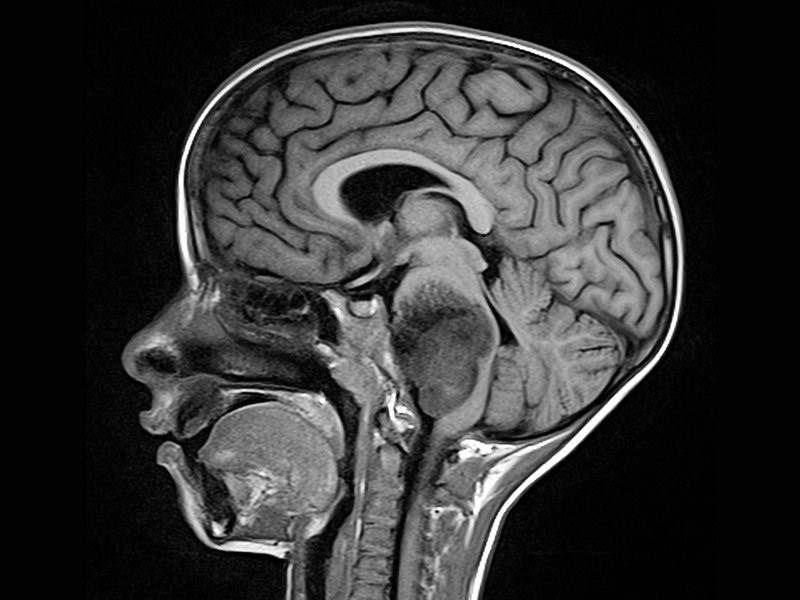

在许多中心,作为临床肿瘤成像的支柱,对比增强CT已经逐渐被磁共振成像所取代。肿瘤高强度开启T2序列[包括自旋回波和流体衰减反转恢复(FLAIR)]反映了与...